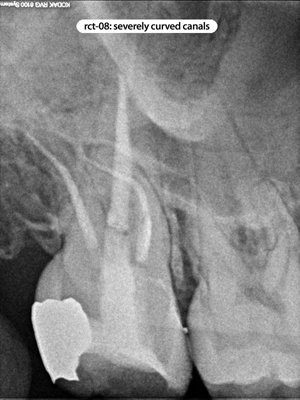

Root Canal Cases